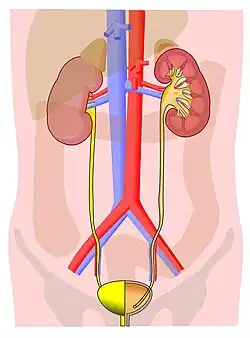

Excretion is elimination of metabolic waste, which is an essential process in all organisms. In vertebrates, this is primarily carried out by the lungs, kidneys, and skin.[1] This is in contrast with secretion, where the substance may have specific tasks after leaving the cell. For example, placental mammals expel urine from the bladder through the urethra,[2] which is part of the excretory system. Unicellular organisms discharge waste products directly through the surface of the cell.

In animals, the main excretory products are carbon dioxide, ammonia (in ammoniotelics), urea (in ureotelics), uric acid (in uricotelics), guanine (in Arachnida), and creatine. The liver and kidneys clear many substances from the blood (for example, in renal excretion), and the cleared substances are then excreted from the body in the urine and feces.[6]